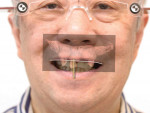

A 65-year-old man presented with concerns about quality of life with regard to his oral condition. Due to deterioration of his maxillary and mandibular fixed and removable appliances and remaining supporting teeth (Nos. 6, 8, 12, 27 through 29, and 31), he was unable to eat adequately (Figure 1 and Figure 2). His chief desire was to have a fixed prosthesis.

Dentofacially, with the patient smiling, the maxillary gingival margins were not visible. However, the patient's mandibular teeth Nos. 27 through 31 (No. 30 being a pontic) were supererupted and fully visible in the patient's smile (Figure 3). The dentofacial risk was assessed as high and the prognosis poor.